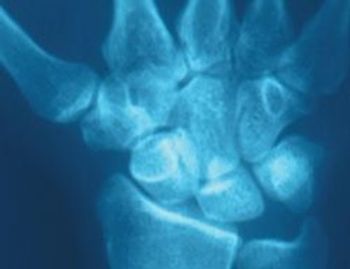

She caught herself with her hands in a forward fall. A year later, her wrist is still painful. What should be done?

A 55-year-old American Indian truck driver presentedwith a 2-day history of right wrist swelling and pain. He denied previous trauma to the wrist or having performed unusual activities.